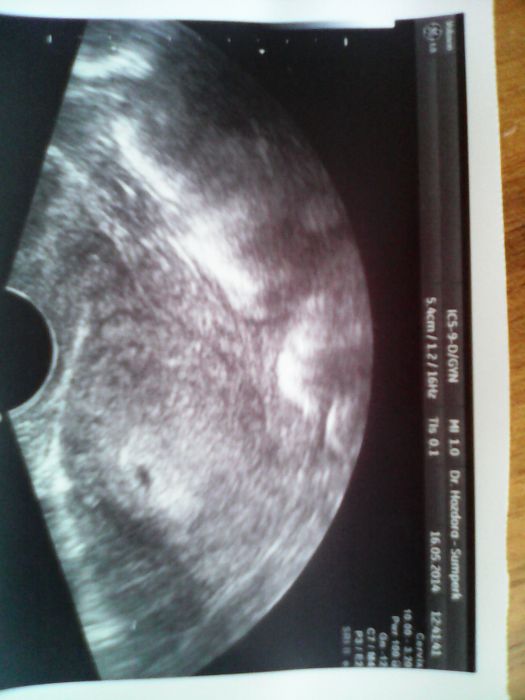

Přikládám foto